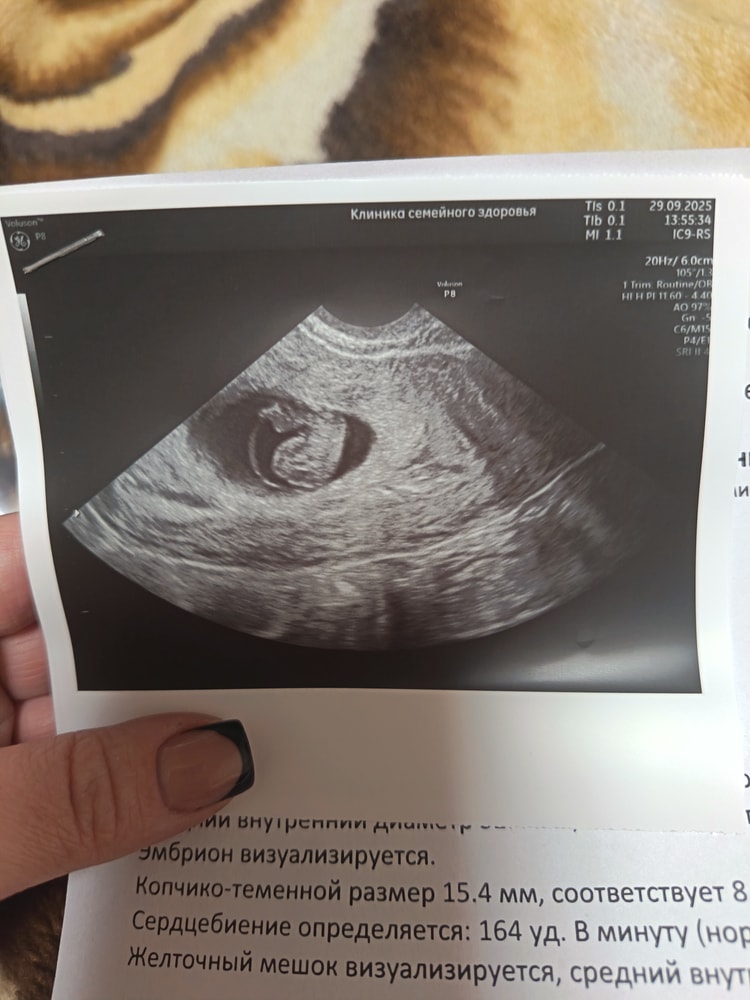

Была сегодня на УЗИ, всё отлично, эмбриончик есть, сердечко дали послушать. Насчёт выделений, врач сказал гематом нет, отслойки нет, просто где-то сосудик лопнул(возможно резко встала или ещё что-то). Вообщем мы безумно рады, расти наша кроха🙏🏻😍💕

Ух ты, это в 8 недель так хорошо человечка на УЗИ видно?) Я тоже так хочу💕🥰Поздравляю вас)) Растите здоровенькими 🥰